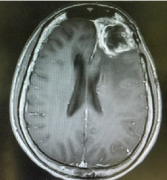

功能區(qū)膠質瘤怎么治?左側額顳島葉膠質瘤治療實例

流行病學研究顯示,島葉膠質瘤占全部低級別膠質瘤的25%和全部高級別膠質瘤的10%...